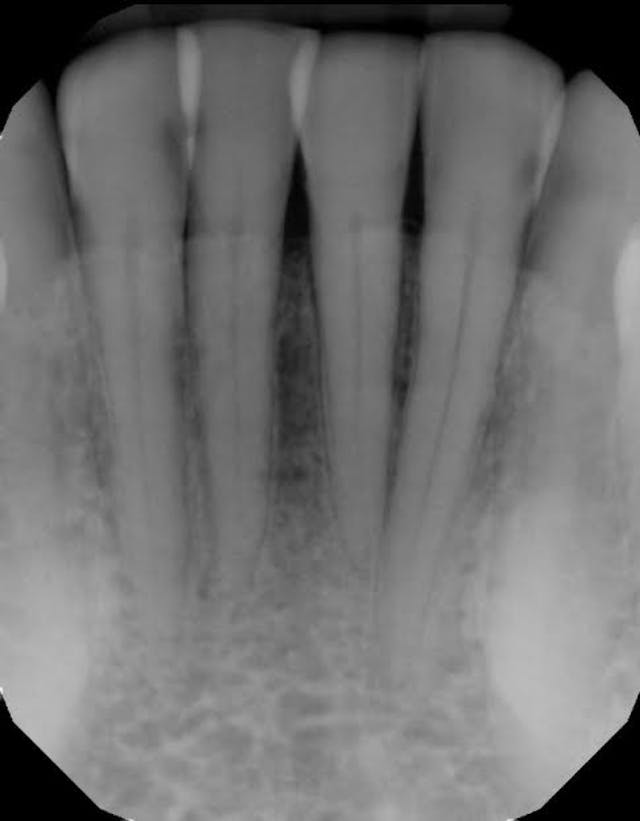

For example, one patient of a general dental practice had a caries-free history for 35 years. He ceased smoking traditional cigarettes and decided to vape as he thought this was a healthier alternative. Within a year, cervical enamel demineralization and interproximal lesions were present on the mandibular anterior sextant, consistent with the primary point of contact of the e-liquid aerosol (figure 2).

Figure 2: Effects of e-cigarette usage